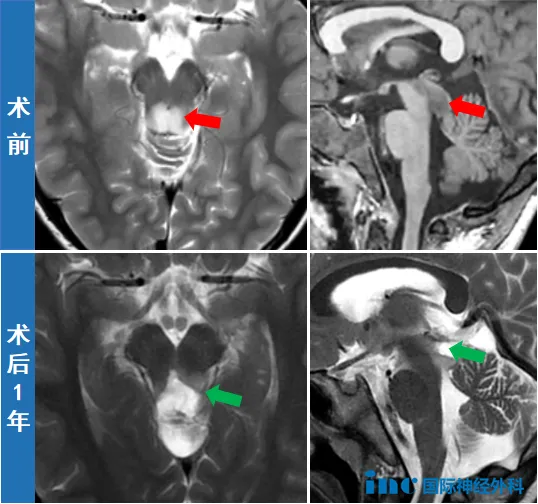

异常信号位于脑干中脑背侧,疑似胶质瘤。此时一家人才后知后觉,原来孩子的头痛、呕吐并不是单纯的感冒这么简单……为了进一步诊断,一家人带着晓飞来到北京,CT以及MRI再次确认中脑顶盖占位,大小约181214mm,边界不清,医生怀疑为低级别胶质瘤。

然而,由于肿瘤位置特殊,毗邻多个重要脑组织,包括中脑导水管、松果体、小脑、丘脑等,术中容错率几乎为0,否则会造成斜视、听力下降、走路不稳等严重后果,手术风险极大,因此医生建议随访观察。

数天后,正值巴教授来华示范手术,晓飞成为当期众多患者中的一个。手术室内,盈盈微光,仿佛照亮了男孩的求生之路。在巴教授的主刀下,手术顺利完成,成功切除肿瘤。术后病理显示为低级别神经上皮肿瘤,一般预后良好。

术后近1年的随访中,巴教授感叹道:“看到男孩目前极佳的临床状况,真的令人欣喜。总而言之,这是一个非常令人满意的进展,我很高兴看到这名男孩处于如此好的情况。”